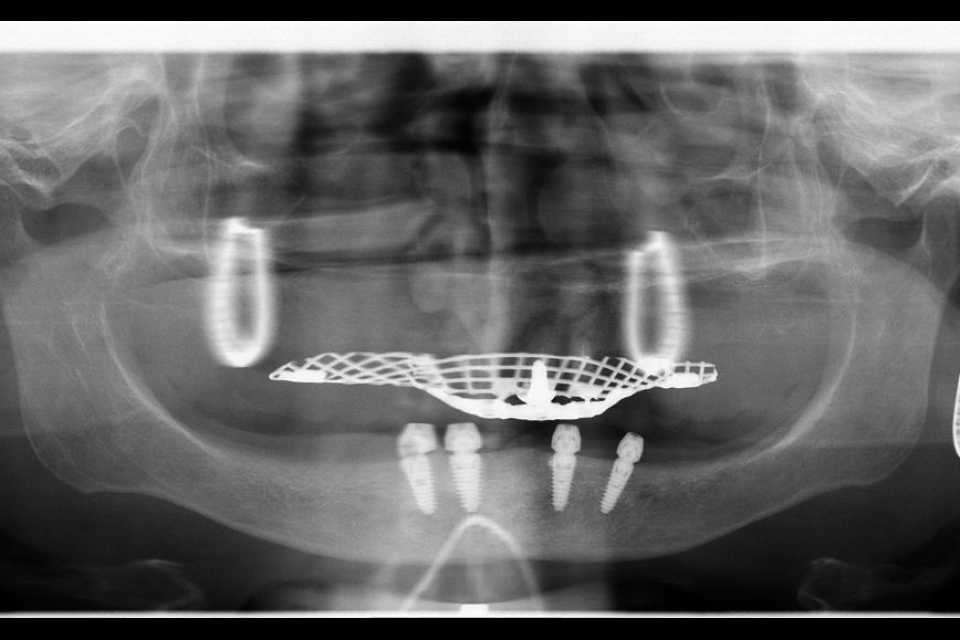

Implanturi AnyRidge inserate interforaminal

Cu ajutorul a 4 implanturi dentare Mega-Gen AnyRidge, inserate interforaminal (tehnica All-on-4), realizăm o lucrare din ceramică pe suport de titan, formată din 12 elemente, înșurubabilă pe suport multiunit.